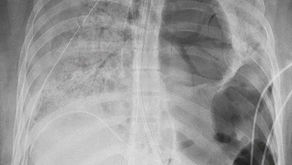

Impactante: le trasplantan los dos pulmones a joven de 20 años por el Covid-19